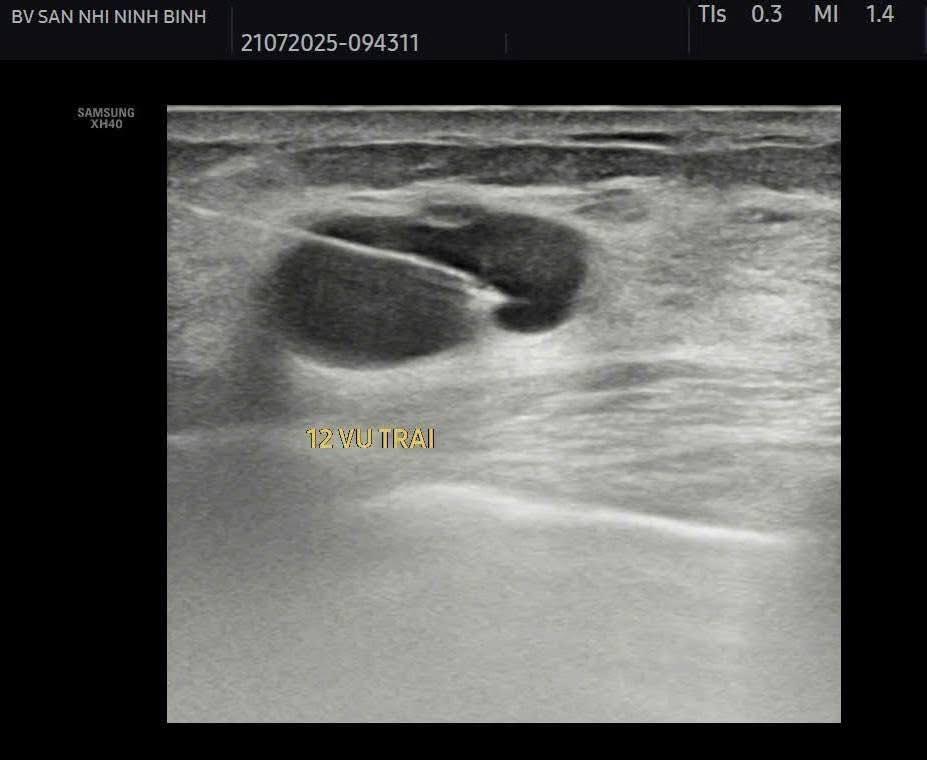

Điều trị diệt nang vú bằng các phương pháp can thiệp tối thiểu như tiêm cồn hoặc các chất gây xơ hóa sau chọc hút nang là phương pháp ít xâm lấn và tỷ lệ tái phát thấp.

Hiện bệnh viện Sản Nhi Ninh Bình đã thực hiện phương pháp điều trị tiêm xơ nang tuyến vú dưới hướng dẫn siêu âm, thực hiện nhanh chóng, thuận tiện ngay tại khoa Chẩn đoán hình ảnh. Giúp bệnh nhân điều trị hiệu quả, tránh tái phát, không cần vào viện và theo dõi tại nhà dưới sự hướng dẫn, dặn dò kĩ càng của bác sỹ điều trị trực tiếp.